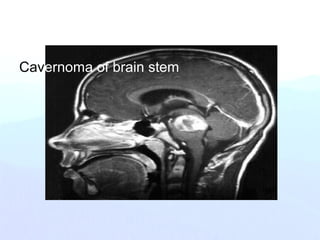

Cavernoma of brain stem